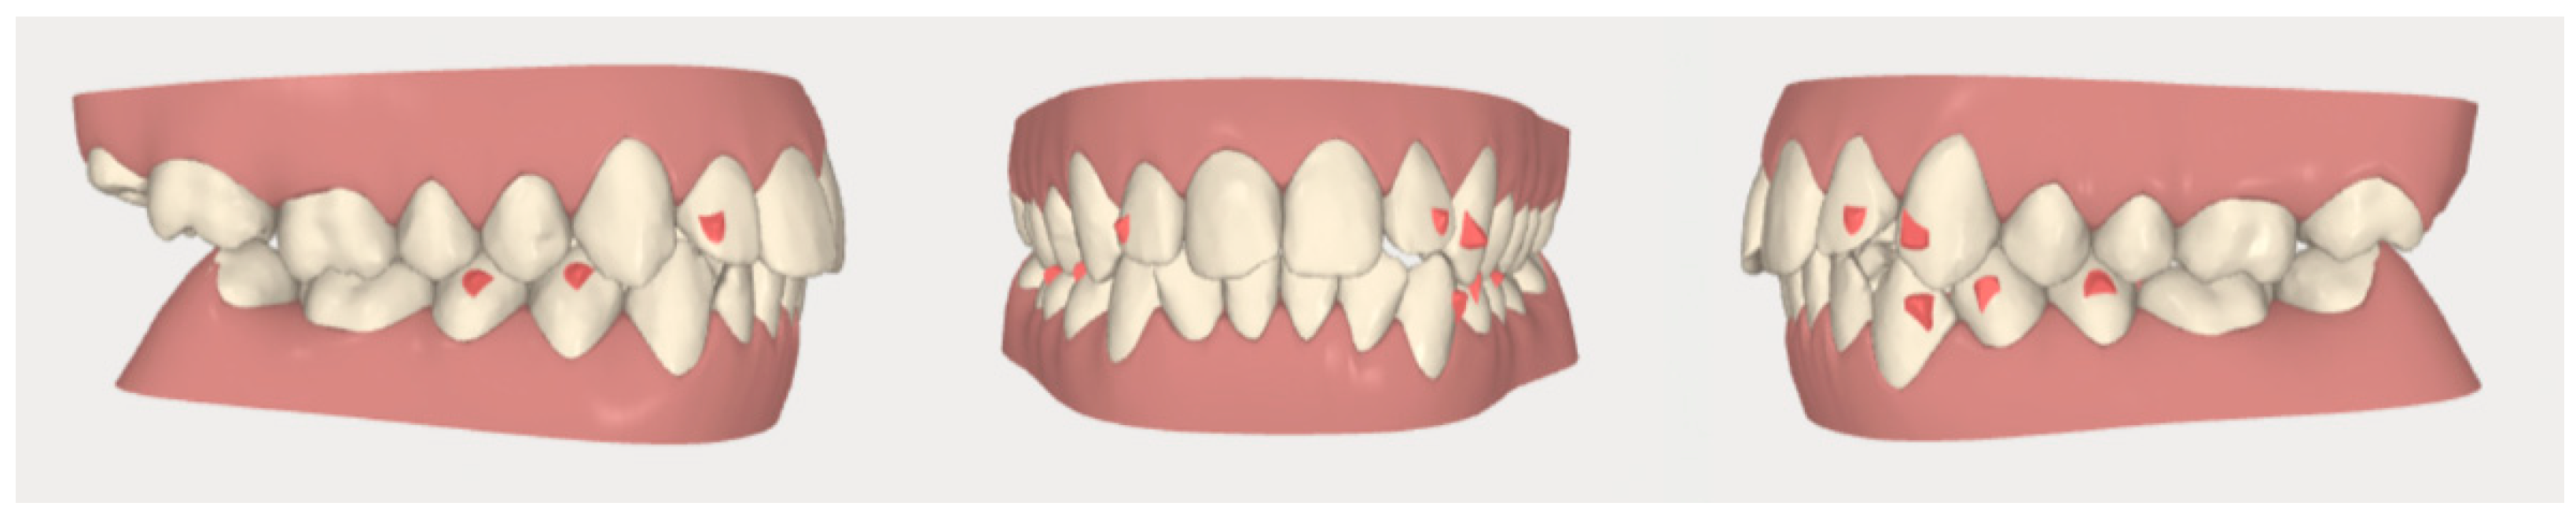

2.2. Orthodontic Planning

2.3.2. Example 2—Extraction Space Closure